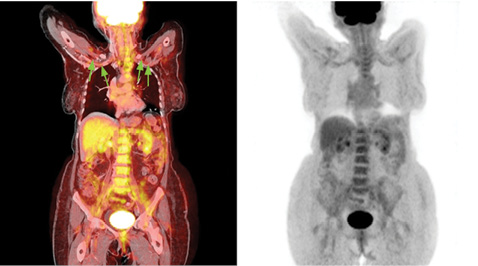

ПЭТ/КТ с контрастным усилением от 24.07.2016 г. Внутривенно введено 18F-ФДГ — 284.79999 МБк. При исследовании метаболически активной неопластической ткани не выявлено. Однако установлено повышение фиксации РФП стенками аорты, надаортальными, подвздошными и бедренными артериями (SUVmax от 3,15 до 4,8); стенка аорты утолщена до 0,4 см (SUVmax аорты = 4,6) (рис. 1–3). Согласно данным ПЭТ/КТ, у пациентки Б. наблюдалось выраженное поражение подключичных артерий со многочисленными стенозами, поражение восходящей аорты, дуги и нисходящей аорты, подвздошных и бедренных артерий. Наибольшее накопление РФП отмечено в подключичных артериях. Поражение различных артериальных сосудов объясняло разнообразные жалобы пациентки и появление симптомов поражения/выпадения функций. Так, поражение подключичных артерий ассоциировалось со слабостью в руках, зябкостью, миалгией верхних конечностей, артралгией, несмотря на сохранение пульса на периферических артериях рук. Поражение сонных артерий — с нарушениями зрения, головной болью, головокружением, шаткостью. Поражение абдоминального отдела аорты объясняло многочисленные гастроэнтерологические жалобы пациентки, прежде всего болевой синдром.

Рис. 1.

Комбинированное ПЭТ/КТ- (слева) и ПЭТ-изображения в корональной проекции демонстрируют стеноз обеих подключичных артерий (стрелки) и повышенное накопление РФП вдоль стенок обеих подключичных артерий и нисходящей аорты

Рис. 2.

Корональная проекция ПЭТ/КТ. Стеноз подключичных артерий (зеленые стрелки) и повышенное накопление РФП вдоль стенок обеих подключичных артерий, нисходящей аорты и подвздошных артерий (черные стрелки)